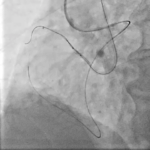

Τεχνικές Προσπέλασης για τη Διάνοιξη χρόνιων ολικών αποφράξεων

Η ορθόδρομη προσπέλαση αποτελεί την πλέον συχνά χρησιμοποιούμενη τεχνική στη διάνοιξη χρόνιας ολικής απόφραξης. Περιλαμβάνει την προσπέλαση της βλάβης από το εγγύς προς το περιφερικό άκρο της αρτηρίας, ακολουθώντας τη φυσιολογική φορά της αιματικής ροής.

Αν και είναι τεχνικά πιο απλή συγκριτικά με την οπισθόδρομη, ωστόσο η επιτυχία της περιορίζεται σε περιπτώσεις εκτεταμένης ασβέστωσης ή όταν η είσοδος της απόφραξης είναι ασαφής.

Από την άλλη, η ανάδρομη προσπέλαση εφαρμόζεται όταν η ορθόδρομη τεχνική αποτυγχάνει ή θεωρείται υψηλού κινδύνου. Αν και προσφέρει υψηλότερα ποσοστά επιτυχίας σε δύσκολες βλάβες, η ανάδρομη τεχνική απαιτεί μεγάλη εμπειρία και εγκυμονεί αυξημένο κίνδυνο επιπλοκών.